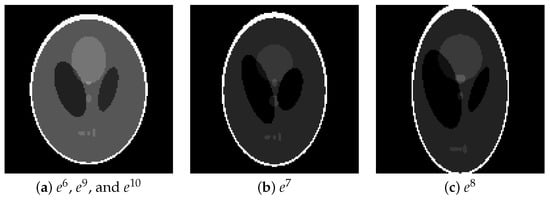

We generated projections , which were magnified versions of projections . These projections were generated from phantoms shown in Figure 12, which were enlargements of . The projection noise level to be applied was the same as in the previous subsection. The number of projection directions was increased to 180 so that the inverse problem would not be unduly difficult due to the large image size . In the proposed use case, the parameters are estimated on the basis of a smaller projection reduced from the larger projection, but here the procedure is inverted. That is, the image reconstruction of projection for any uses the parameter estimated from its smaller version, projection .

Figure 12.

Phantom images of (a) , , and , (b) , and (c) for testing.